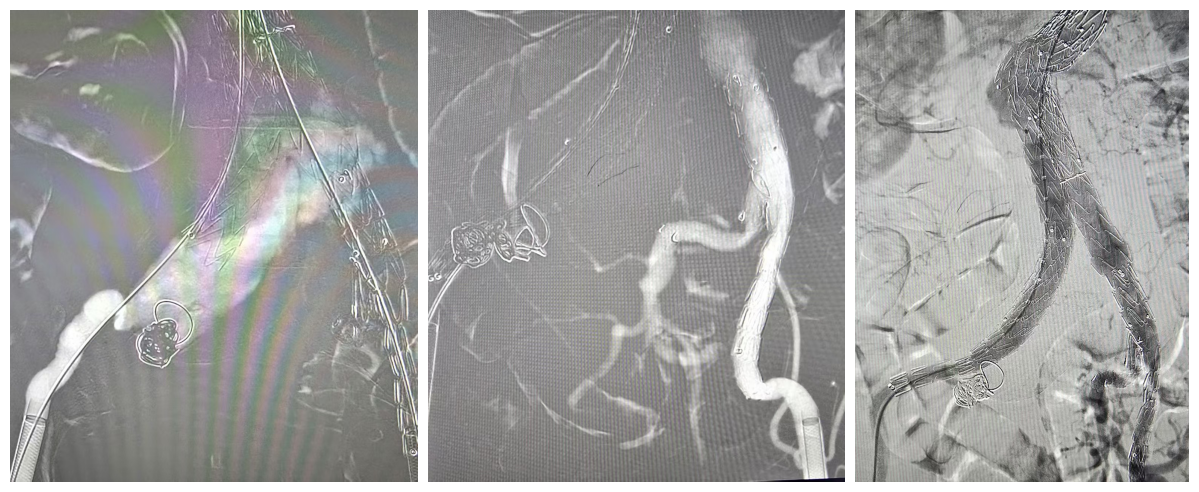

心内科首席专家严金川教授接诊后,组织血管外科、麻醉科、影像科等多学科团队进行会诊,全面评估患者情况。考虑到患者年龄大、瘤体复杂且破裂风险高,团队最终决定为其实施微创介入手术——「腹主动脉-双髂动脉腔内隔绝术」,并同期完成左髂内动脉分叉支架植入与右髂内动脉弹簧圈封堵。

「腹主动脉瘤是指腹主动脉的局部或普遍扩张,90% 发生于肾动脉下方,病因多为主动脉粥样硬化、创伤、感染等,患病者多为老年人群,尤其是 65 岁以上男性。多数患者早期没有明显症状,部分患者可能感到脐周或中下腹部搏动性肿块、钝痛、腰痛、局部压痛。它就像体内的「不定时炸弹」,一旦破裂,死亡率极高。」严金川说,此类复杂病例通常手术难度大、风险高,以往多采取传统开腹手术,创伤大、恢复慢。此次采用的微创介入方式,仅通过微小穿刺口完成操作,极大减轻了患者痛苦,有利于术后康复。

此次手术历时数小时,在多科室通力协作下顺利完成。术后患者生命体征平稳,恢复良好,目前已出院回家。